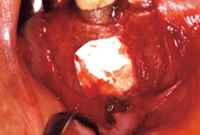

本症例は、側枝による感染根管の可能性も考えられたが、瘻孔からポイントを挿入して撮影したX線写真がメタルコア下部を指していたことから、歯根破折の可能性が高いと考えた。そこで、実際に患部の歯肉弁を剥離して歯周状態を確認したところ、歯頸部から5mmほど下縁に楕円状の骨の裂開が認められ、歯根近心中央部分に垂直性歯根破折を確認した(図❹)。

図❹ 3部の歯肉弁を剥離したところ、歯根中央部分に垂直性歯根破折(矢印)を確認した